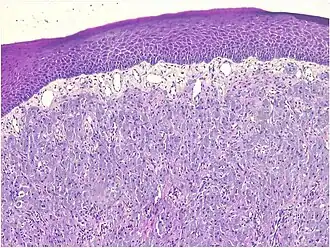

Histopathological Characteristics

Histopathologically, congenital epulis is usually characterized by the presence of big, rounded cells that fill the mucosa's lamina propria and have round to oval nuclei and an abundance of eosinophilic cytoplasm.[10] A thin layer of connective tissue separated the surface layer of cells from the growing new cells. Numerous histological traits, such as a fibrous and granulomatous appearance, have been reported in recent research.[10]

Microscopically, congenital epulis is composed of:

- Sheets of proliferating polygonal to round cells with overlying thin squamous, eosinophilic, granular cytoplasm[12][13]

- Centrally located, round nuclei [7]

These histopathological features are essential in distinguishing congenital epulis from other gingival and soft tissue neoplasms.